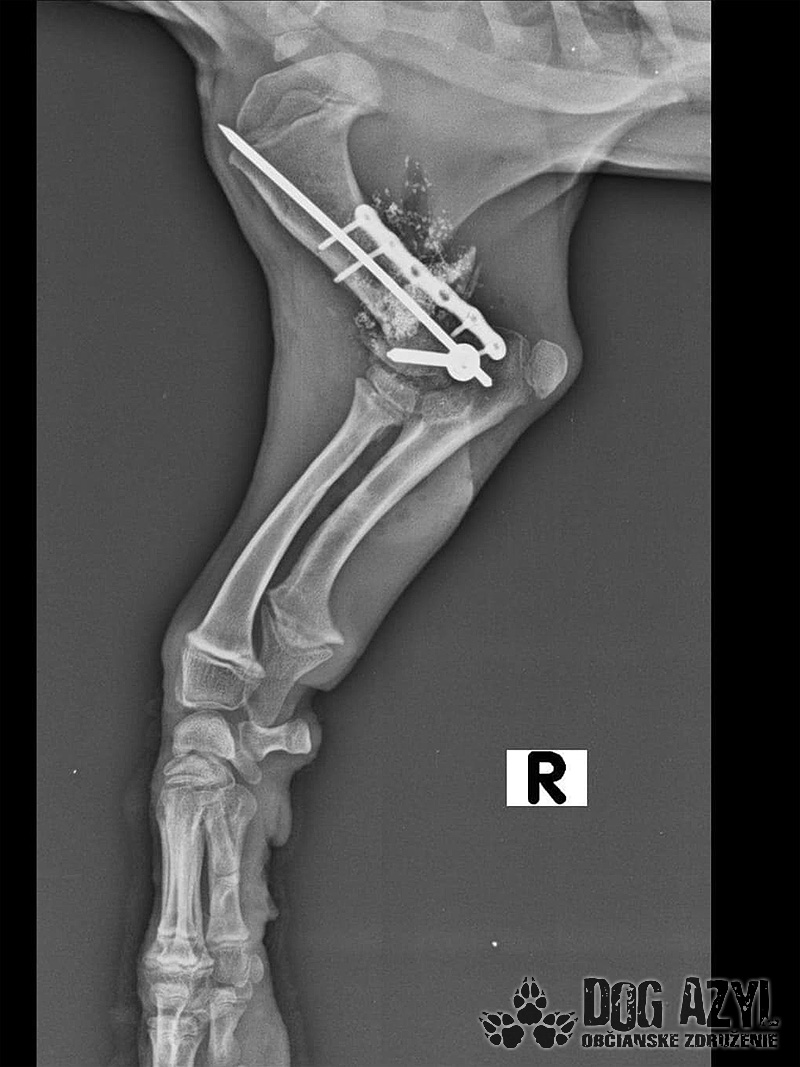

Pluto dnes absolvoval druhú operáciu. Vyberala sa platnička a veľká skrutka, ktorá sa nahradila menším pinom. Koncom mesiaca ho čaká ďalšia a dúfame, že už posledná operácia. Také malinké šteniatko a už toľko bolesti musí prežívať :( Má sa dobre, rastie do krásy a už sa pomaly može naplno šantiť so svojim kamošom v dočasnej opatere. :) Veľmi pekne prosíme, pomôžte nám s úhradou faktúr. Faktúry nájdete priebežne v galérii a na konci článku aj zoznam darcov s prijatou aj chýbajúcou sumou. Po poslednej operácii čakajú Pluta ešte mesiace rehabilitácie, aby sa nožička úplne rozhýbala a mohol ju používať naplno :)

Odoberal sa od drogovo závislých asociálov, ktorý boli vysťahovaný z domu. Ihly, striekačky, ľudské výkaly, rôzne neidentifikovateľné zvratky, špinavé oblečenie, použité kondómy - to všetko nahádzané na jednu kopu v obývačke, kde Pluto so svojou maminkou Miou žili. :( Nevieme ako sa to stalo, kto mu ublížil, ale Pluto má prestrelenú prednú nohu! Viete si predstaviť toho psychicky narušeného človeka, ktorý strieľa na malé bezbranné šteniatko? V dôsledku strelnej rany má doslova rozdrvenú lakťovú kosť. Mali sme veľké obavy, že o nožičku príde, ale MVDr. Vatolík s teamom veterinárnej kliniky Sibra centrum opäť urobil zázrak a malému nožičku napravil a prognóza je viac než dobrá. Čaká ho ešte dlhá cesta k zotaveniu, ale je to odvážny a statočný bojovník. Nechceme si ani len predstaviť čím všetkým si tie zvieratká muesli prejsť, a kto vie koľko ich pôvodne bolo.. Nikto nevie ako a kde skončili Plutovi súrodenci...